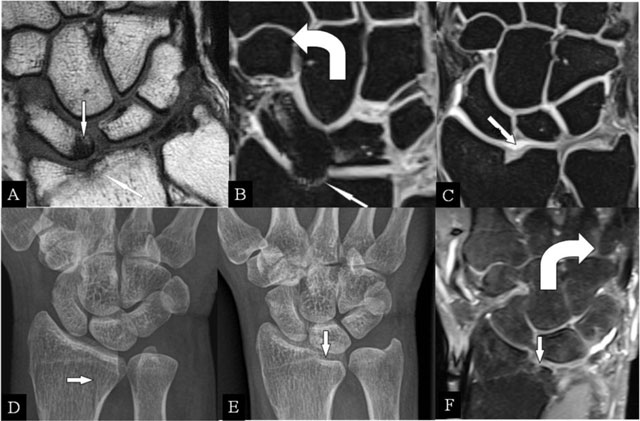

Figure 1

Radioscafoid and radiolunate abutment. (A) Coronal SE T1-WI; (B, C) Coronal 3D-GRE; (D, E) PA plain radiographs; and (F) Coronal SE PD-WI FS. (A) Sequela of an intra-articular fracture of the distal radial epiphysis with a residual step-off (oblique arrow) and marrow oedema (vertical arrow) at the proximal pole of the scaphoid bone. (B) Centrally, the cartilage is destroyed and the radial deviation is blocked. (C) Cartilage step-off in another patient. (D) The parasagittal intra-articular fracture was initially missed. (E) Consolidation with a depressed part of the articular surface. (F) Radiolunate abutment with blocked ulnar deviation.